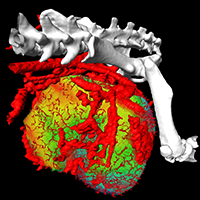

The Science Council Session at this year’s AAPM Annual Meeting focuses on “The Physics of Cancer,” emphasizing fundamental science in understanding how cancer originates, its progression, and its response to treatment. Among the presentations is work by Dr. Robert Jeraj and colleagues at the University of Wisconsin on anti-angiogenic therapy. This emerging form of cancer treatment works by stopping tumors from making new blood vessels, and new research suggests that molecular imaging can be used to help doctors make more informed decisions about its use. Understanding how tumors respond to anti-angiogenic therapies is key to improving a patient’s treatment efficacy. Dr. Jeraj is using molecular imaging, such as FLT PET/CT, to better understand how anti-angiogenic therapies will stop or slow rapid tumor growth.

The Science Council Session at this year’s AAPM Annual Meeting focuses on “The Physics of Cancer,” emphasizing fundamental science in understanding how cancer originates, its progression, and its response to treatment. Among the presentations is work by Dr. Robert Jeraj and colleagues at the University of Wisconsin on anti-angiogenic therapy. This emerging form of cancer treatment works by stopping tumors from making new blood vessels, and new research suggests that molecular imaging can be used to help doctors make more informed decisions about its use. Understanding how tumors respond to anti-angiogenic therapies is key to improving a patient’s treatment efficacy. Dr. Jeraj is using molecular imaging, such as FLT PET/CT, to better understand how anti-angiogenic therapies will stop or slow rapid tumor growth.